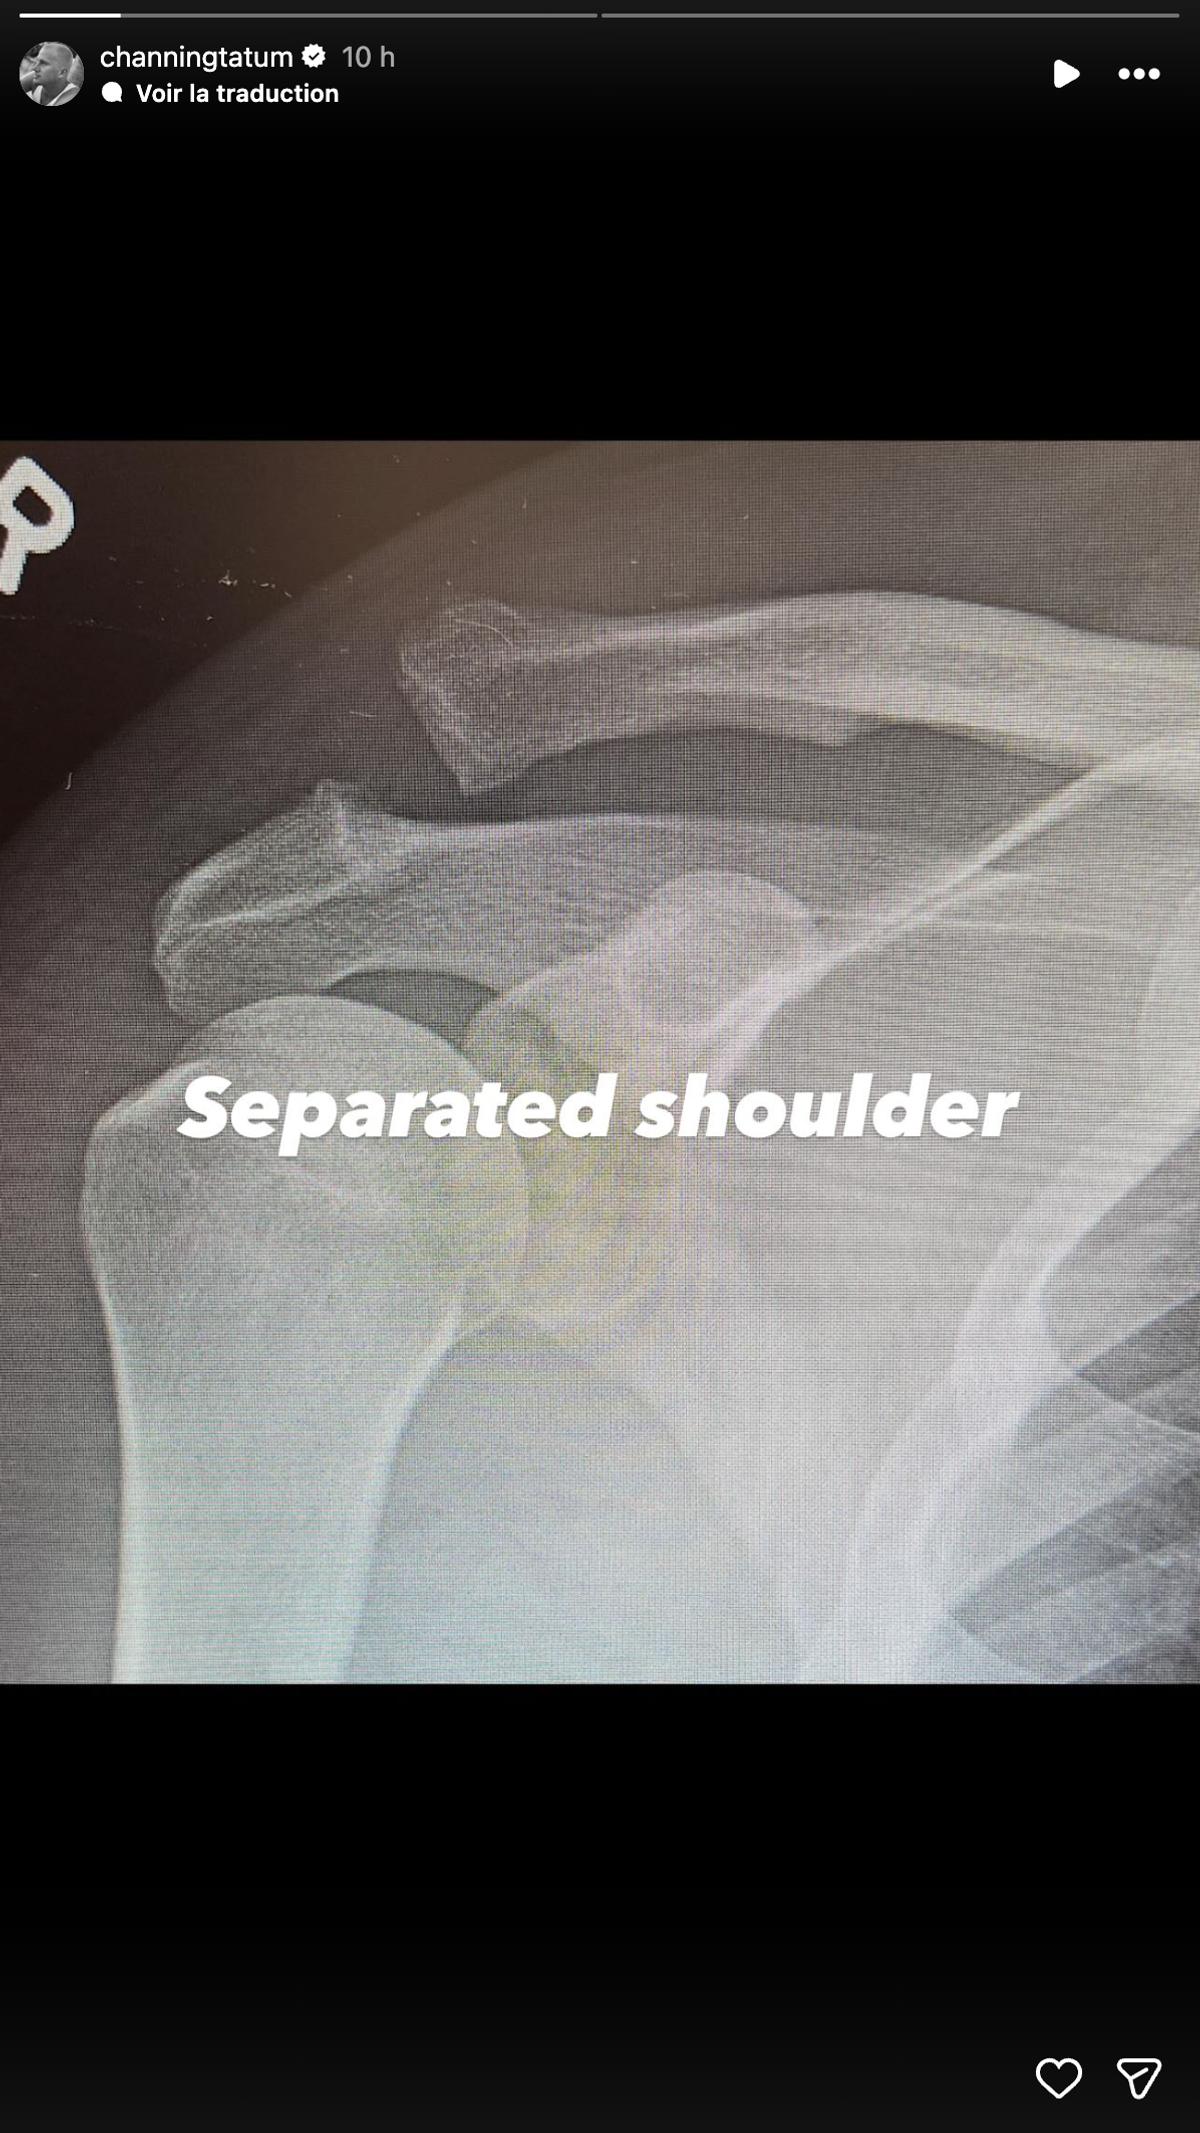

Fidèle à son habitude de jouer la carte de la transparence, la vedette de Magic Mike n'a pas caché les détails graphiques de son intervention. Il a partagé des radiographies avant et après l'opération qui ne laissent place à aucun doute : on y voit clairement deux os fracturés, puis une grosse vis maintenant le tout en place.

Avec son humour habituel, Channing a simplement commenté la radiographie de son épaule réparée par un ironique : «Épaule vissée. Youpi». Il a précisé qu'il s'agissait d'une réparation pour une «luxation de l’épaule» et une luxation congénitale.